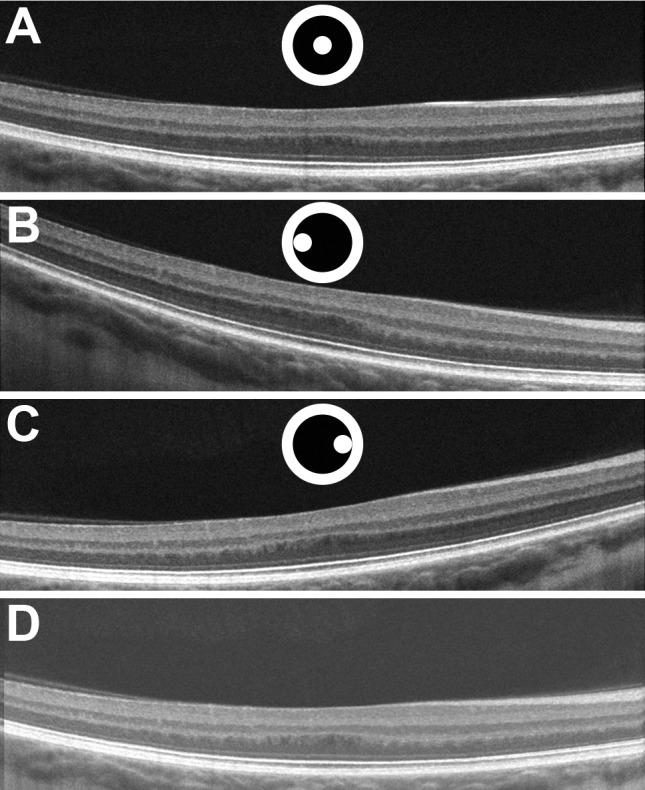

Directional optical coherence tomography (D-OCT) allows the visualization of the Henle fiber layer (HFL) in vivo. Here, we used D-OCT to characterize the HFL and outer nuclear layer (ONL) in albinism and examine the relationship between true foveal ONL and peak cone density.

Horizontal D-OCT B-scans were acquired, registered, and averaged for 12 subjects with oculocutaneous albinism and 26 control subjects. Averaged images were manually segmented to extract HFL and ONL thickness. Adaptive optics scanning light ophthalmoscopy was used to acquire images of the foveal cone mosaic in 10 subjects with albinism, from which peak cone density was assessed.

Across the foveal region, the HFL topography was different between subjects with albinism and normal controls. In particular, foveal HFL thickness was thicker in albinism than in normal controls (P < 0.0001), whereas foveal ONL thickness was thinner in albinism than in normal controls (P < 0.0001). The total HFL and ONL thickness was not significantly different between albinism and controls (P = 0.3169). Foveal ONL thickness was positively correlated with peak cone density in subjects with albinism (r = 0.8061, P = 0.0072).

Foveal HFL and ONL topography are significantly altered in albinism relative to normal controls. Our data suggest that increased foveal cone packing drives the formation of Henle fibers, more so than the lateral displacement of inner retinal neurons (which is reduced in albinism). The ability to quantify foveal ONL and HFL may help further stratify grading schemes used to assess foveal hypoplasia.